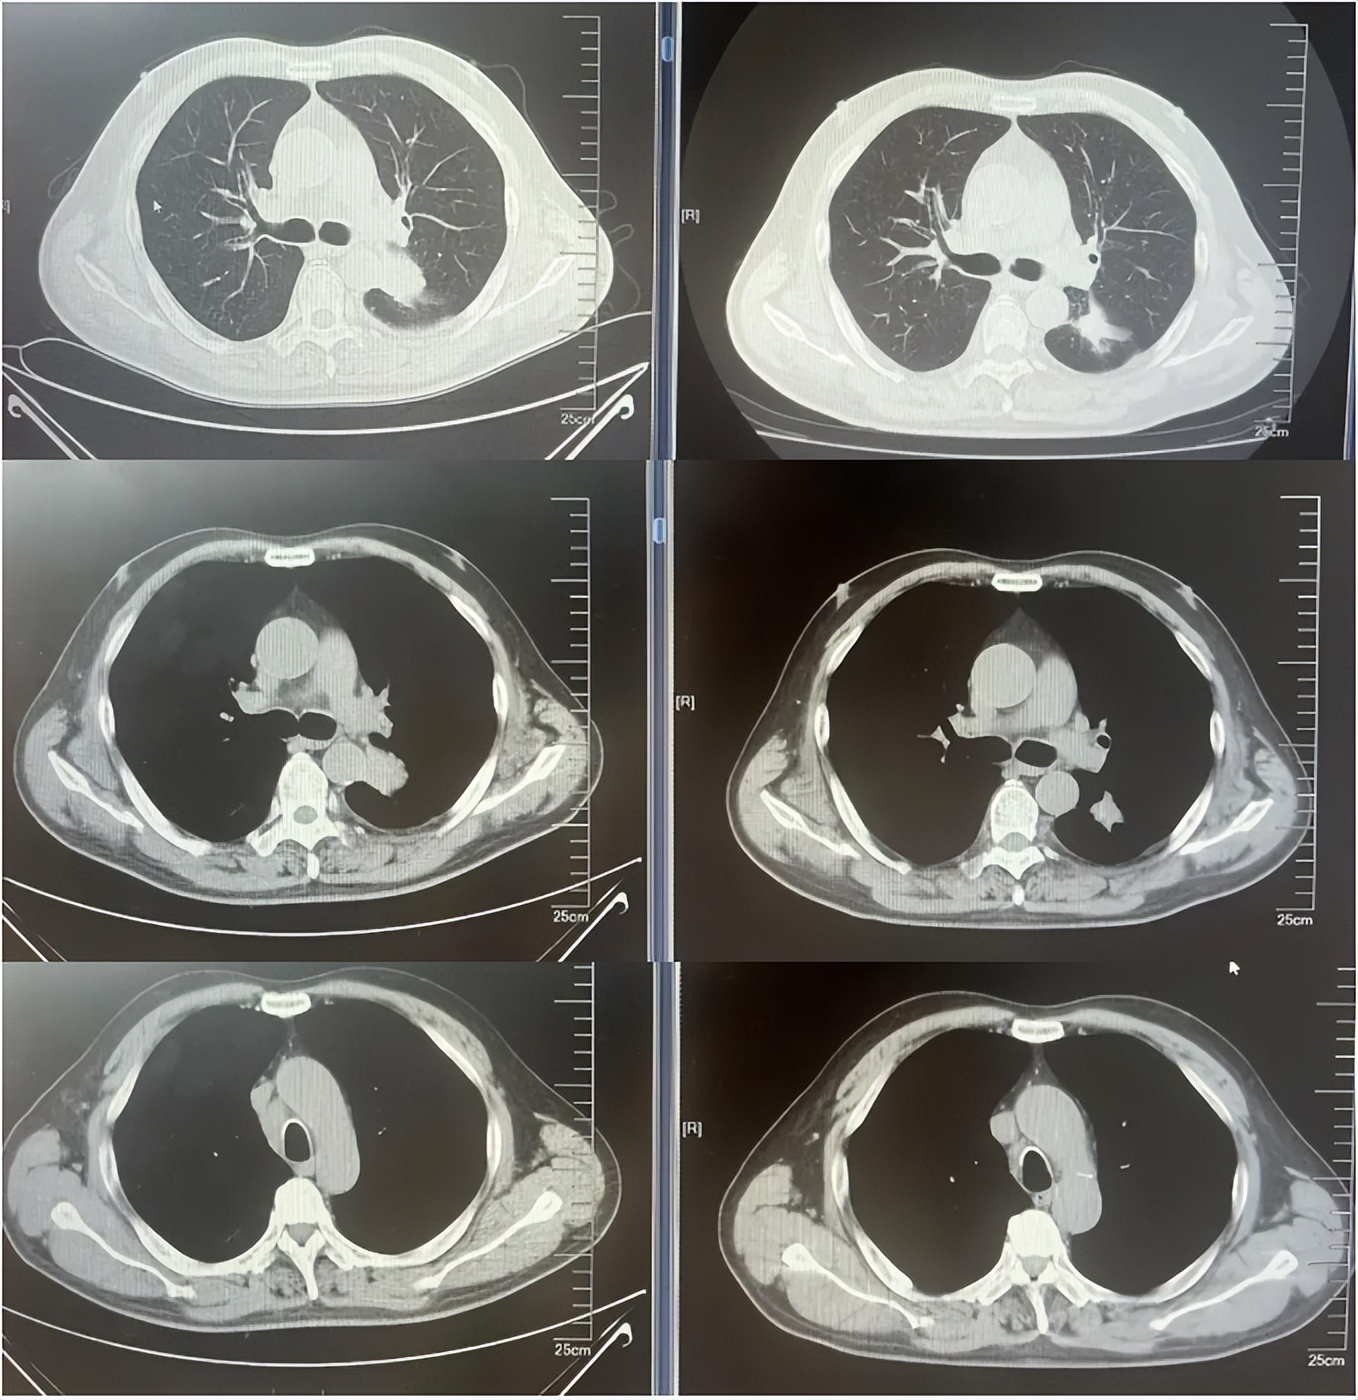

病例1治疗经过

病例2:患者男,61岁。2023年8月于外院行肺CT提示:右肺下叶肿块。2023年10月23日于我院行单孔胸腔镜下右肺下叶切除术、肺门纵隔淋巴结扩清术。术后病理:腺癌低分化(腺泡型占30%,乳头型占30%,筛状占30%,微乳头占10%)。分期pT4N0M0 IIIA期。术后行基因检测提示HER2+(14%),PD-L1 2%+。术后行AC方案化疗4周期后行阿替利珠单抗维持治疗1年。末次用药时间:2024年11月1日。2025年2月复查肿瘤标志物升高,肺HRCT示:双肺多发结节,考虑转移。行血液基因检测提示:ERBB2 35.5%突变,CDK1 9.5%突变,MDM2 4.92%突变。患者DFS 14m,阿替利珠单抗停药后3个月出现复发转移,可见传统免疫治疗效果不佳。恰逢德曲妥珠单抗一线新尝试DESTINY-lung 04研究公布了入组标准和治疗方案,且该患在术后的组织基因检测和复发后的血液基因检测中都明确存在HER2突变,故行德曲妥珠单抗一线治疗。最佳疗效PR,目前治疗持续有效,PFS超过6个月。无药物相关不良反应发生。

德曲妥珠单抗治疗4周期(2025.4)疗效对比